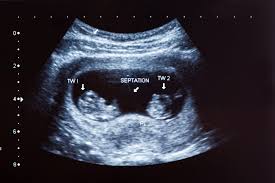

By 8 weeks pregnant your womb is around the size of a lemon too small to show but you re still going to be feeling the effects of pregnancy. An ultrasound can confirm the presence of multiple pregnancies. For others the 8 week ultrasound is the first time you see your baby. It almost looks like.